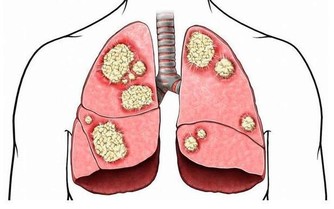

過量維生素K會導致人體出現癌症和長疹的現象。孕婦服用大劑量維生素K會造成新生兒黃疸。服用含維生素K量高的多種維生素亦影響口服抗凝劑的效果。

有人主張長期服用大劑量維生素C預防感冒和癌症,及降血脂等,但應嚴防過量中毒。